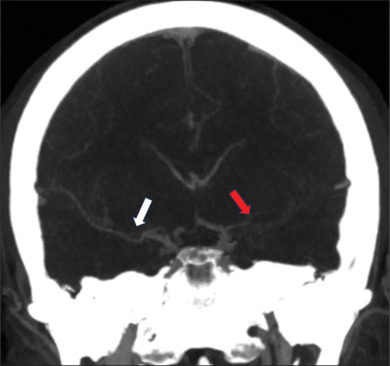

烟雾病(MMD)是一种以颅内动脉进行性闭塞为特征的脑血管疾病,常导致脑卒中和脑出血。虽然烟雾病通常影响颅内血管系统,但我们报告了一个不寻常的双侧椎体狭窄闭塞病例,导致37岁烟雾病患者椎基底动脉功能不全,并通过血管成形术和椎动脉支架置入术治疗。回顾文献显示椎动脉近端受累是烟雾病的罕见表现。该报告有助于了解烟雾病的临床谱,并强调需要警惕和意识到受影响个体颅内外血管并发症的可能性。

Moyamoya disease (MMD) is a cerebrovascular disorder characterized by progressive occlusion of intracranial arteries, often leading to stroke and intracerebral hemorrhage. While MMD classically affects the intracranial vasculature, we present an unusual case of bilateral vertebral steno-occlusion, resulting in vertebrobasilar insufficiency in a 37-year-old man with MMD and treated with angioplasty and stenting of the dominant vertebral artery. Review of the literature demonstrates proximal vertebral artery involvement to be a rare manifestation of moyamoya disease. This report contributes to the understanding of the clinical spectrum of MMD and emphasizes the need for vigilance and awareness of the possibility of extracranial vascular complications in affected individuals.